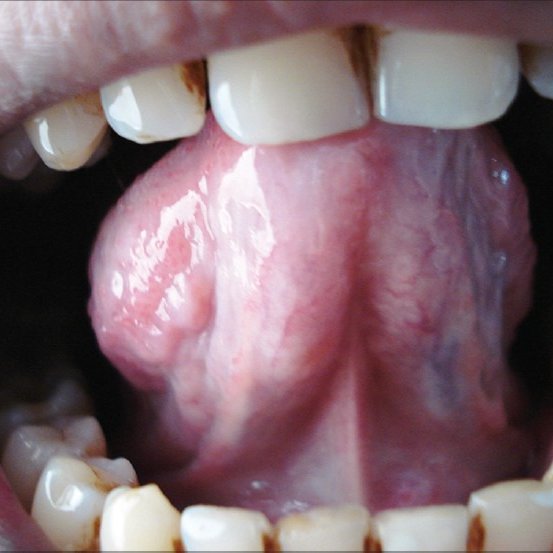

The main symptom of oral submucous fibrosis is leathery appearance of oral mucosa (soft tissue lining the oral cavity). It begins from posterior or backmost part behind the molars and gradually extends towards the lip. The other signs are xerostomia (dry mouth or limited salivation), multiple ulcerations, burning sensation of the mouth, decreased movement of soft palate, pigmentation of lips and mucosa, thinning of lips, pain in the ear and deafness, inability to eat and difficulty in mouth opening and speech.

Stage 2: fibrosis: appearance of leathery patches in the posterior part of oral cavity. The patch extends towards the lip like palpable fibrous bands with a marble like appearance resulting in muscle trismus.